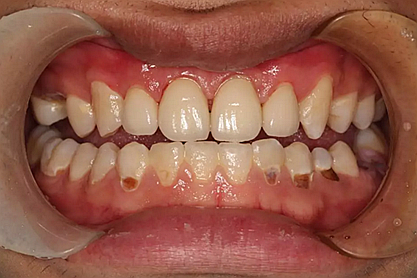

現(xiàn)在剩下的任務就是為我其他的兄弟姐妹們治療了。需要做根管的做根管,需要做冠的做冠,需要樹脂充填的做樹脂充填。前前后后主人帶我們進行了12次的復診,歷時6個月,現(xiàn)在的我們是這樣的

再來看看曾經的我們